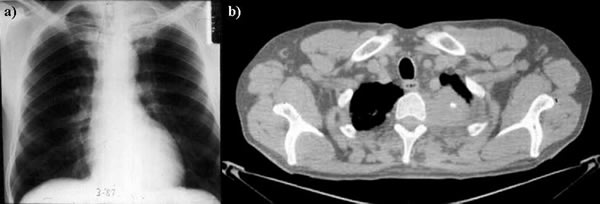

Рентгеновские снимки опухоли Панкоста